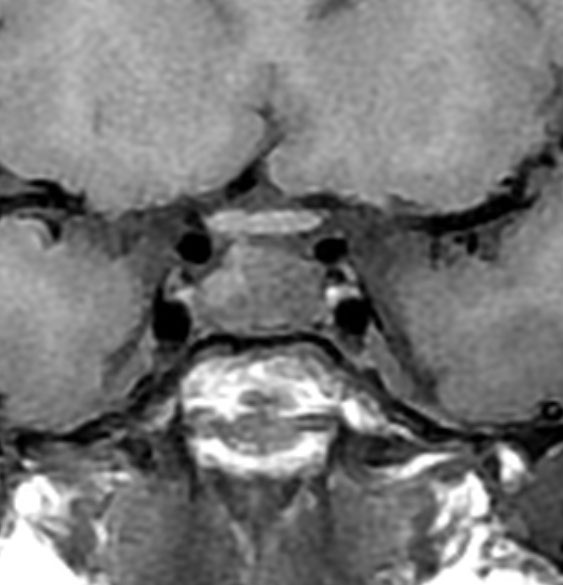

多少取り残しても再発しない

29歳の女性が高プロラクチン血症による月経不順で発症しました。視野検査では両耳側半盲が認められました。

手術所見では,多量のコレステリン結晶が流出しました。腫瘍実質は硬く正常下垂体との剥離はできませんでした。黄色肉芽種の可能性もあるので,あ全摘出にとどめて手術を終了しました。T2強調画像で黒い低信号の縁取りがあり内部に不均一なのう胞内容液が見えるのが特徴とも言えます。

3年後の画像です。腫瘍の再燃増大はありませあん。視野は正常化して,下垂体機能も正常化しホルモン補充はありません。